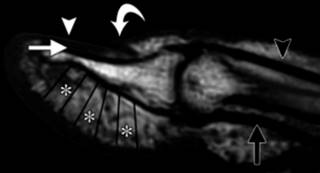

El felón, también conocido como panadizo, es un absceso del pulpejo del dedo. Generalmente se originan por inoculación directa, aunque no siempre se logra documentar un traumatismo penetrante. Debido a que el pulpejo consiste en múltiples compartimentos fibrosos delimitados por septos (Figura 4), la presión puede aumentar suficientemente para provocar necrosis grasa y de la piel.

Figura 4: Imagen por resonancia magnética, corte sagital obtenido en T1. Se observa la compleja anatomía de la punta digital. Se distingue la lámina ungueal (cabeza de flecha), la matriz estéril (flecha blanca), el eponiquio (flecha curveada), los septos verticales de la punta digital (asteriscos), el tendón flexor (flecha negra) y el tendón extensor (cabeza de flecha negra).